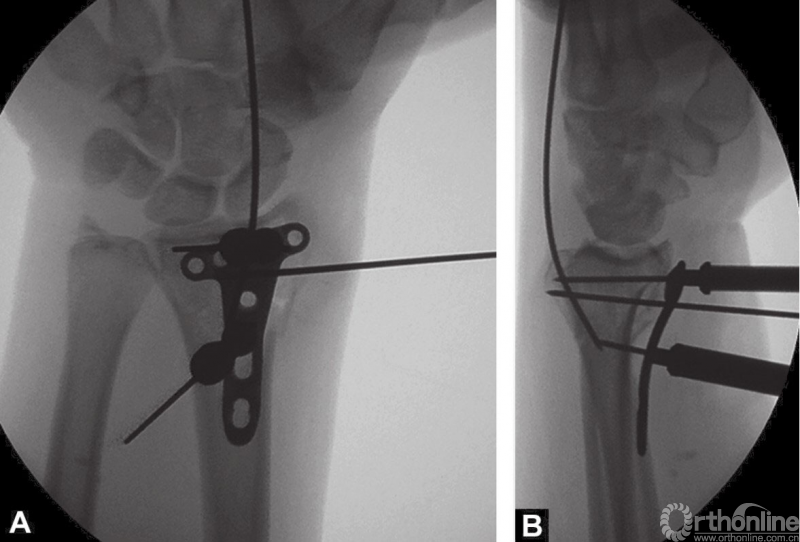

首先牵引复位骨折,1.4mm克氏针从桡骨茎突钻入临时固定骨折(图3),通过背侧置入克氏针撬拨技术复位背侧塌陷骨块,X线透视检查骨折复位情况。

图3 术中透视复位克氏针临时固定

2.4mm桡骨远端T形锁定钢板安放锁定套筒后,置入桡骨远端掌侧面,克氏针通过套筒将钢板临时固定在桡骨远端(图4A和B)。

图4 A和B桡骨远端放置2.4mm锁定钢板和用克氏针临时固定